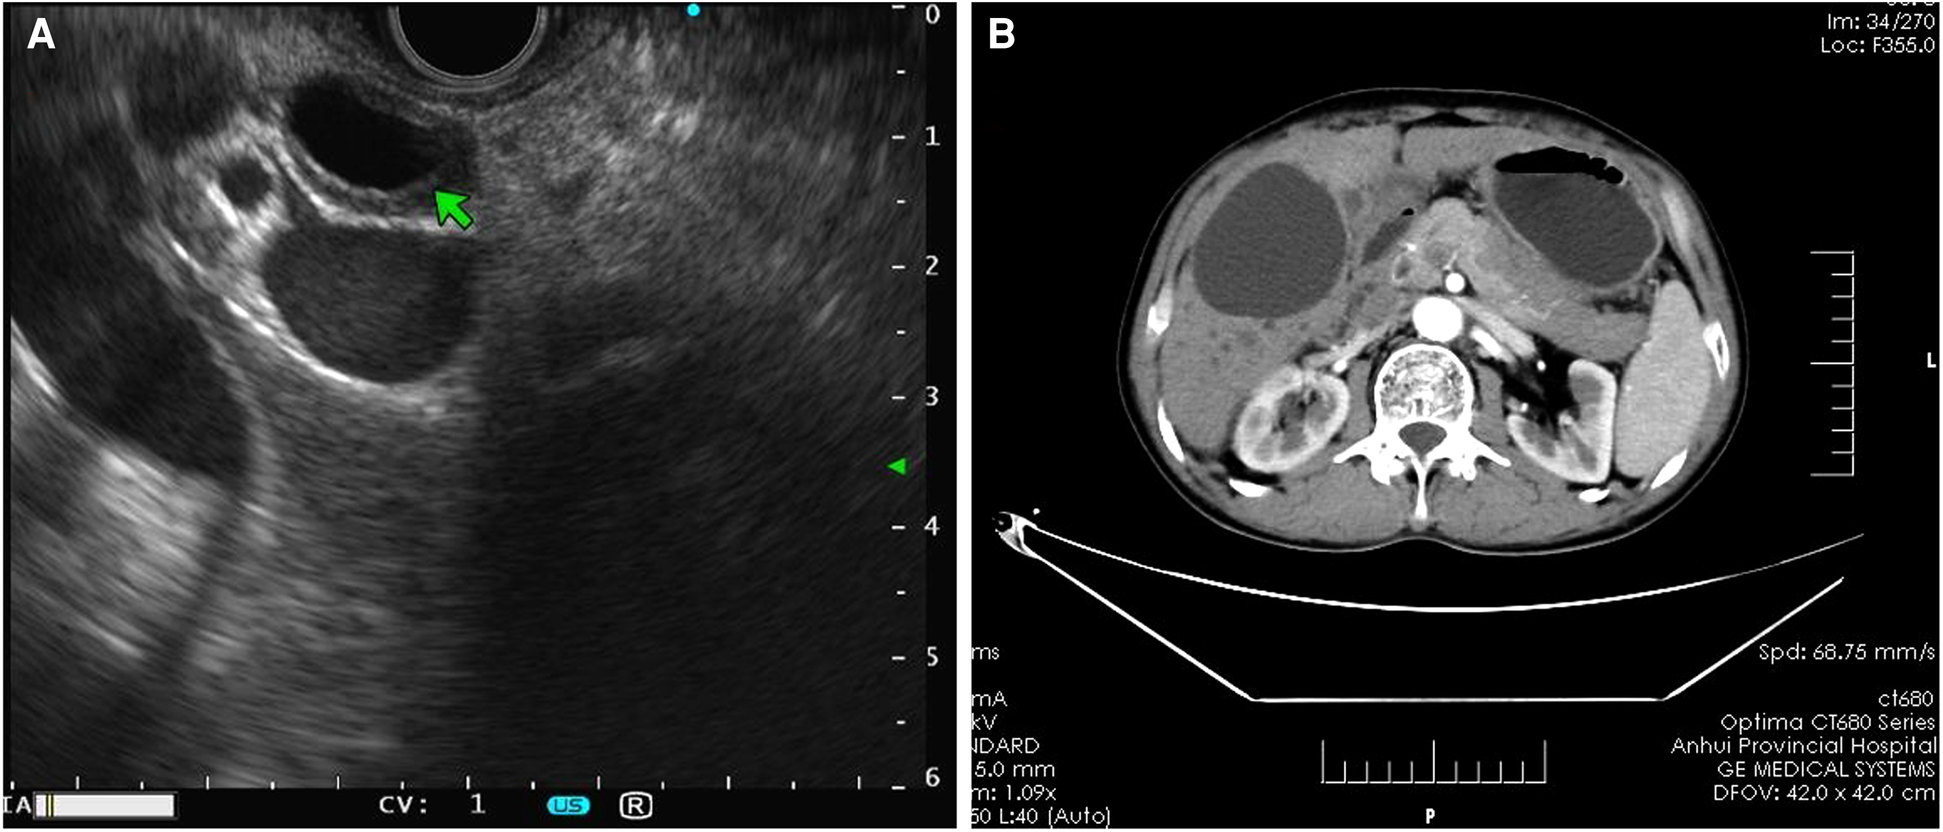

Patients with AIP and pancreatic cancer experienced lymph node hyperplasia and swelling in the abdominal cavity and retroperitoneum (P > 0.05). In 16 (72.73%) patients with AIP, lesions were detected in the bile ducts, which were accompanied by autoimmune cholangitis. Only 3 (10.00%) patients with pancreatic cancer had lesions in the common bile duct. There were significant differences in bile duct wall thickness and tube occupation between patients with AIP and patients with pancreatic cancer. The typical EUS images of AIP showed bile duct wall thickening, pancreatic mass lesions, irregular narrowing of the main pancreatic duct, and bile duct dilatation (Figure 2).

FIGURE 2

www.frontiersin.org

Figure 2. Imaging features of AIP. (A) Endoscopic ultrasound revealed bile duct wall thickening and common bile duct dilatation with the bilateral sign in patients with AIP. (B) Computed tomography scan showed an even thickening of the common bile duct wall, evident enhancement in the arterial phase, and uneven and irregular enhancement of the head and neck areas. AIP, autoimmune pancreatitis.